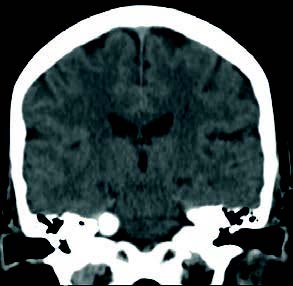

Mujer de 76 años con un traumatismo craneal y pérdida de conciencia. Cuatro meses antes le detectaron en un TAC craneal una formación calcificada en ángulo pontocerebeloso.

Mujer de 76 años con un traumatismo craneal y pérdida de conciencia. Cuatro meses antes le detectaron en un TAC craneal una formación calcificada en ángulo pontocerebeloso. Tiene antecedentes de vértigos posicionales desde hace años por problemas de columna. Fue operada de una tumoración lipomatosa grande en la espalda hace 2 años y desde entonces tiene una contractura. Refiere pérdida de audición antigua, más intensa por oído derecho, y ahora también tiene pérdida de olfato.

En la exploración, los tímpanos son normales y la audiometría presenta una hipoacusia sensorial bilateral de 50 dB de media en OD y de 45 dB en OI, con caída en agudos. Se pide RMN craneal.